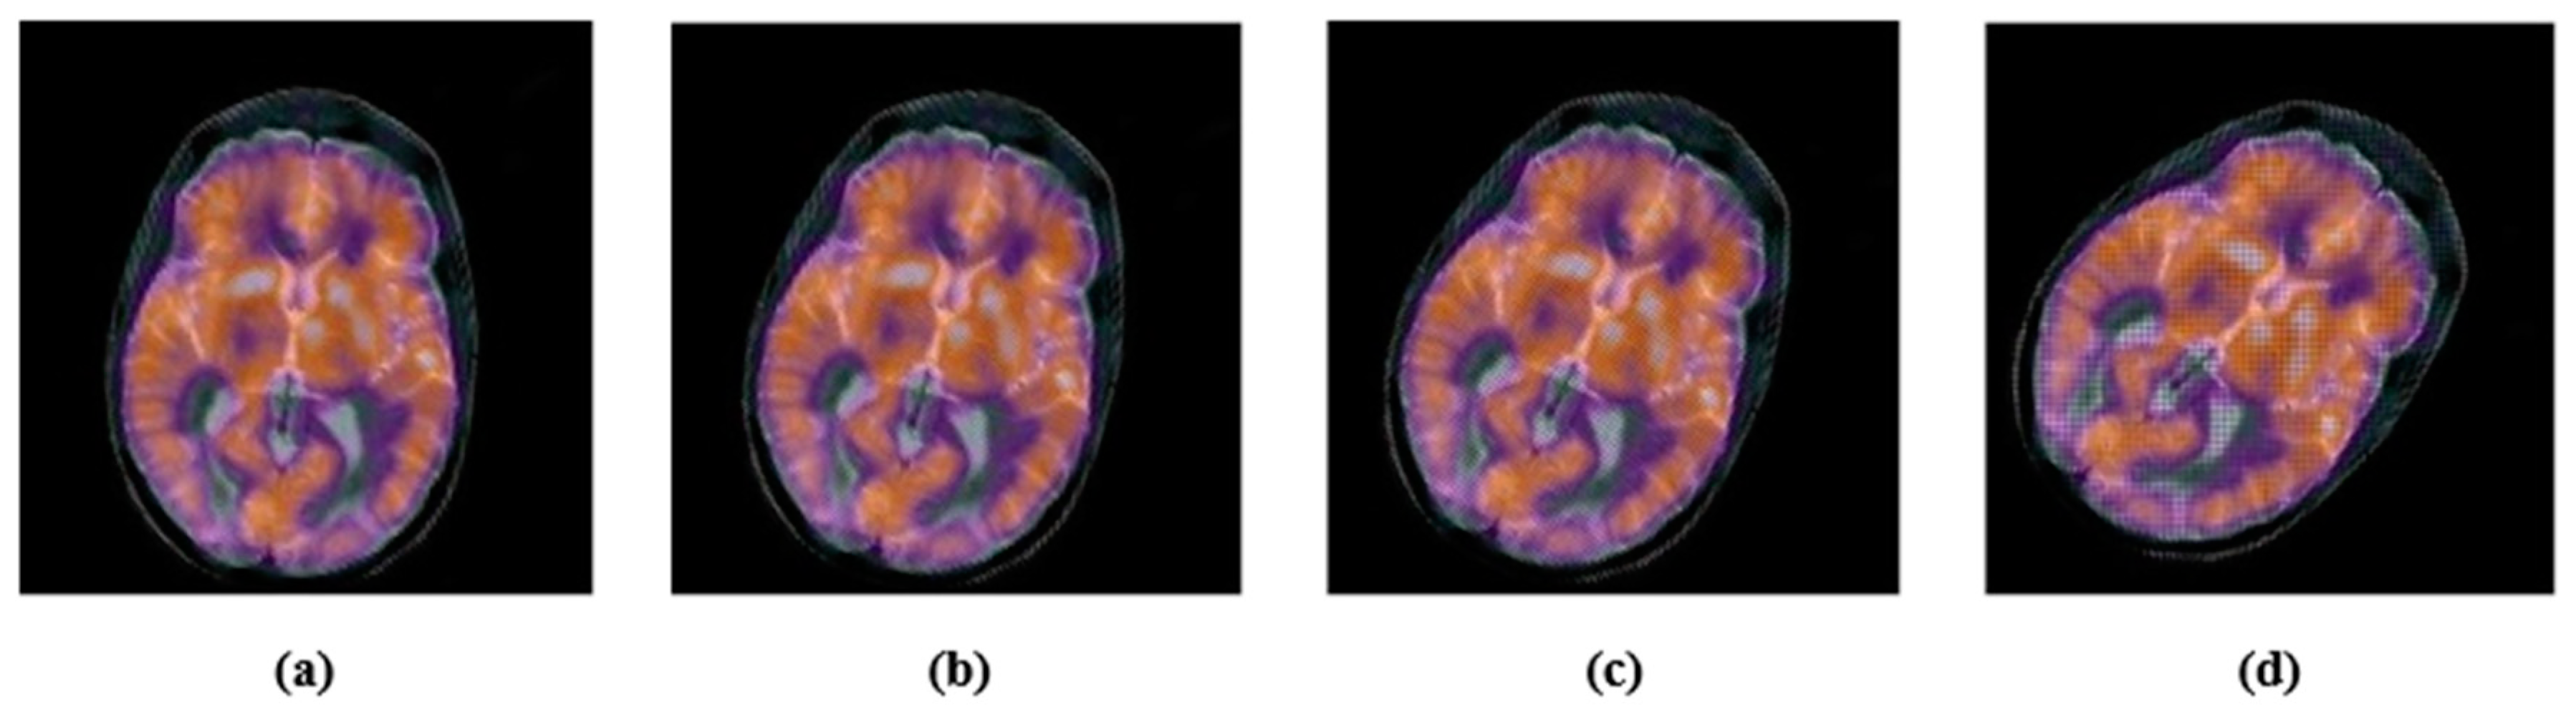

| Image rotation | Rotation angles: 50, 150, 250, 450 |

| Image scaling | Scaling factors: 0.5, 0.75, 1.25, 1.5 |

| Length–width ratio changing | Factor (1.0, 0.75) and (0.5, 1.0). Note: The parameters refer to vertically and horizontally scaling. |

| Image flipping | Vertical and horizontal |

| Applied Attack | Scaling# 0.5 | Scaling# 0.75 | Scaling# 1.5 | Scaling# 2.0 |

| Extracted watermark | ![]() | ![]() | ![]() | ![]() |

| BER | 0.0029 | 0.0020 | 0.0010 | 0 |

| NC | 0.9936 | 0.9957 | 0.9979 | 1.0000 |

| Applied Attack | LWR (1.0, 0.75) | LWR (0.5, 1.0) | Horizontal-flipping | Vertical- Flipping |

| BER | 0.0049 | 0.0068 | 0.0010 | 0.0010 |

| NC | 0.9892 | 0.9849 | 0.9979 | 0.9979 |